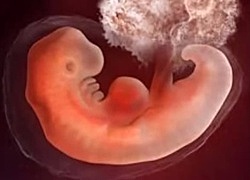

• 22-28 DÍAS -CUARTA SEMANA

22-28 DÍAS -CUARTA SEMANA

El embrión ya esta implantado al útero.

Adquiere una forma humana y tridimensional, sin embargo aun no son notables sus extremidades.

• 29-35 DÍAS QUINTA SEMANA

29-35 DÍAS QUINTA SEMANA

El cerebro del embrión sigue creciendo formándose el tubo neural y encéfalo, ya tiene un sistema nervioso central por ello el tamaño de la cabeza es mayor que el cuerpo.

El embrión mide de de 1 a 2 mm.